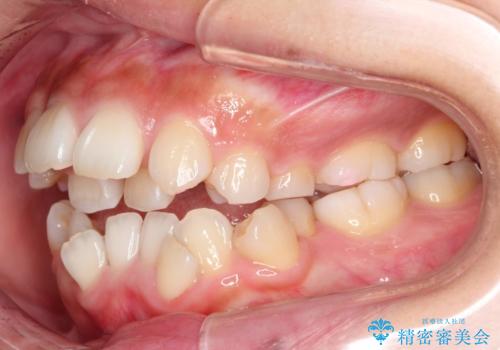

人生が変わる 困難を極める咬合状態に歯列矯正単独で挑戦する

骨格的要因を背景にもつ不正咬合のため、歯列矯正単独での改善は困難と判断しましたが、患者さんとの相談の結果、歯列矯正単独で可能なところまで一緒に頑張りましょうということで、治療をすすめました。

シビアな叢生や開咬も改善することができ、想像以上の改善に時間をかけた甲斐があったと満足していただけました。